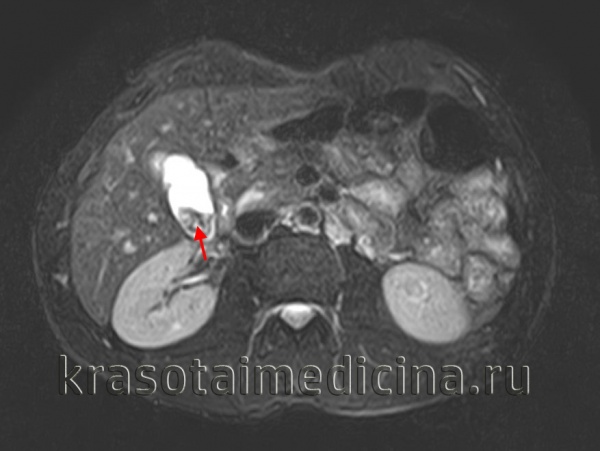

5. МРТ при остром калькулезном холецистите:

• Т1-ВИ:

о Гиперинтенсивный сладж или кровоизлияние в просвете желчного пузыря

• Т2-ВИ:

о Неосложненный холецистит:

- Растянутый желчный пузырь

- Менее интенсивный сигнал от конкрементов и сладжа

- Высокоинтенсивный сигнал от утолщенной стенки и перипузырных тканей

о Осложненный холецистит:

- Дефект утолщенной стенки - при интрамуральном или перипузырном абсцессе

• Т1-ВИ с контрастированием:

о При осложненном холецистите-снижение или отсутствие контрастного усиления

• МР холангиопанкреатография:

о Низкая интенсивность сигнала обтурирующего проток конкремента

МРТ живота. Гипоинтенсивные конкременты в желчном пузыре на фоне умеренно выраженного отека перихолецистических тканей